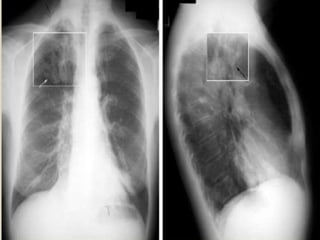

 Signs on CXR include the identification of

parallel linear densities, tram-track opacities, or

ring shadows reflecting thickened and

abnormally dilated bronchial walls. These

bronchial abnormalities form a spectrum from

subtle or barely perceptible 5-mm ring

shadows to obvious cysts. Tubular branching

opacities conforming to the expected bronchial

branching pattern may result from fluid or

mucous filling of bronchi